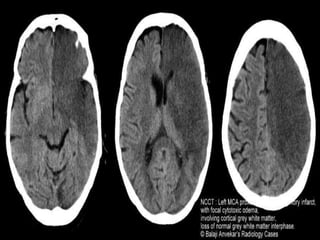

• This differentiation is loss in case of cerebral

odema.

• In true isolated cytotoxic oedema little change

is evident on CT as a mere redistribution of

water from extracellular to intracellular

compartments does not result in attenuation

changes. The changes colloquially ascribed to

'cytotoxic oedema' are in fact mostly due

to ionic oedema, and are described separately.

This is why brain CT is often normal in patients

Cytotoxic

• grey-white matter differentiation is

maintained and the oedema involves mainly

white matter, extending in finger-like fashion

• secondary effects of vasogenic oedema are

similar to cytotoxic oedema, with effacement

of cerebral sulci, with or without midline shift